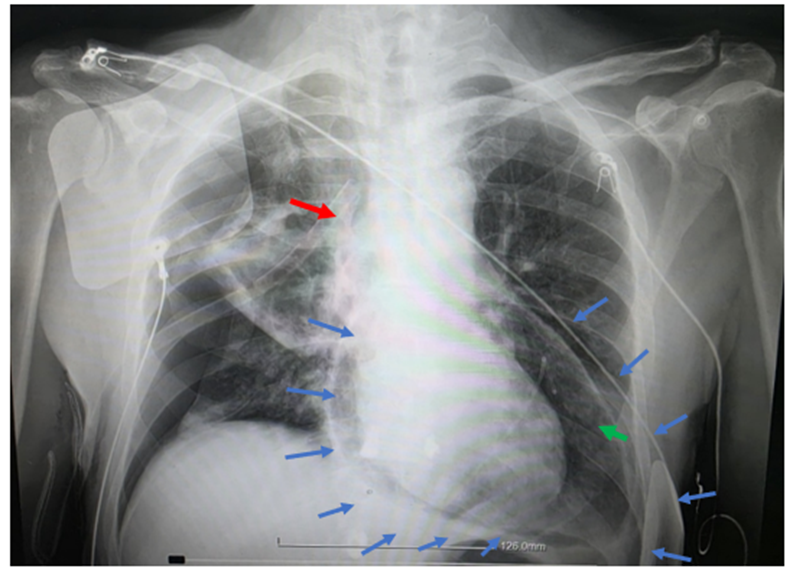

The right pneumothorax was managed with thoracic drainage using a water-seal chest drainage system. Despite this, the patient’s hemodynamics deteriorated, and he developed supraventricular tachyarrhythmia evolving into atrial fibrillation. Invasive arterial monitoring showed pulsus paradoxus. Under echocardiographic guidance, a subxiphoid pericardiocentesis was performed, draining 520 mL of serohemorrhagic fluid. The patient improved transiently after drainage, but air aspiration suggested ongoing communication, and soon the echocardiographic image became obscured due to progressive pneumopericardium. An urgent chest X-ray confirmed extensive air in the pericardial sac. (Figure 3) Clinically, the patient showed transient deterioration due to air accumulation. Therefore, negative-pressure drainage of the pericardial sac using a water-seal chest drainage system was initiated in the absence of a Heimlich valve. Unfortunately, the patient died after 6 hours due to cardiogenic shock and tamponade physiology.

Figure 3: Chest X-ray showing pneumopericardium with concurrent right pneumothorax. Blue arrows define the borders of pericardium. A right pleural drainage tube (red arrow) and a pericardial drainage tube (green arrow) are visible.